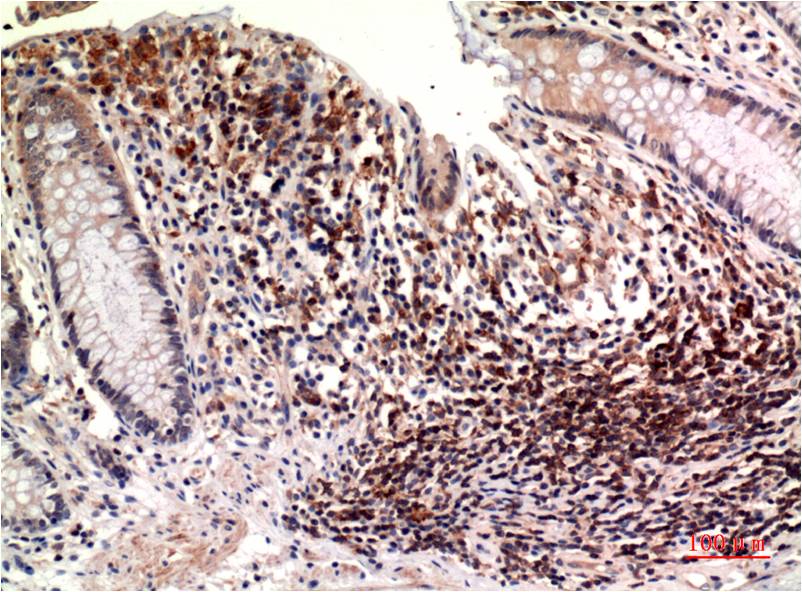

Immunohistochemical analysis of paraffin-embedded Human Colon Carcinoma Tissue using?Epsilon Tubulin(EM1311)Mouse mAb diluted at1:200.